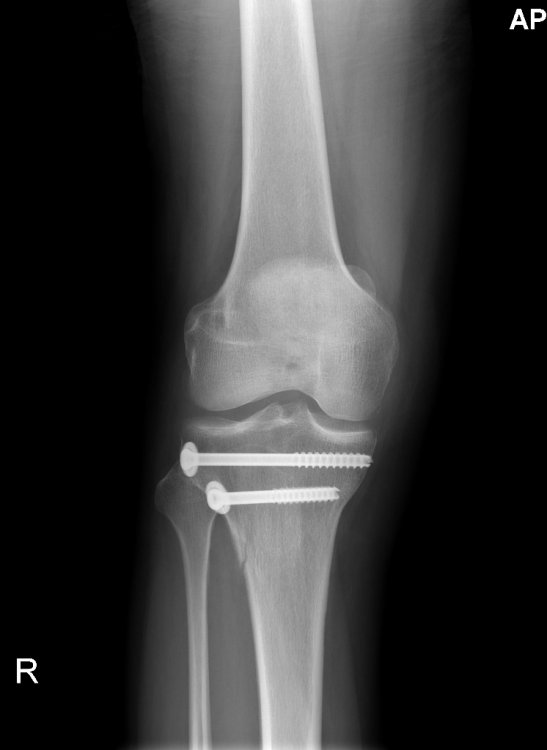

Secondo voi, che chiave occorre per svitare queste viti?

questa è di oggi, appena mi arrivano quelle del ricovero vedi la differenza.

Per precisare: le rondelle sotto la testa ci sono. :2funny:

La vite superiore mi sembra un po lunghetta  :oops:

Vedo male o fuoriesce un pelino fuori dall'osso?

Bel lavoretto, non avrei potuto fare di meglio :alien::2funny:, ma poi quelli viti te le tolgono?